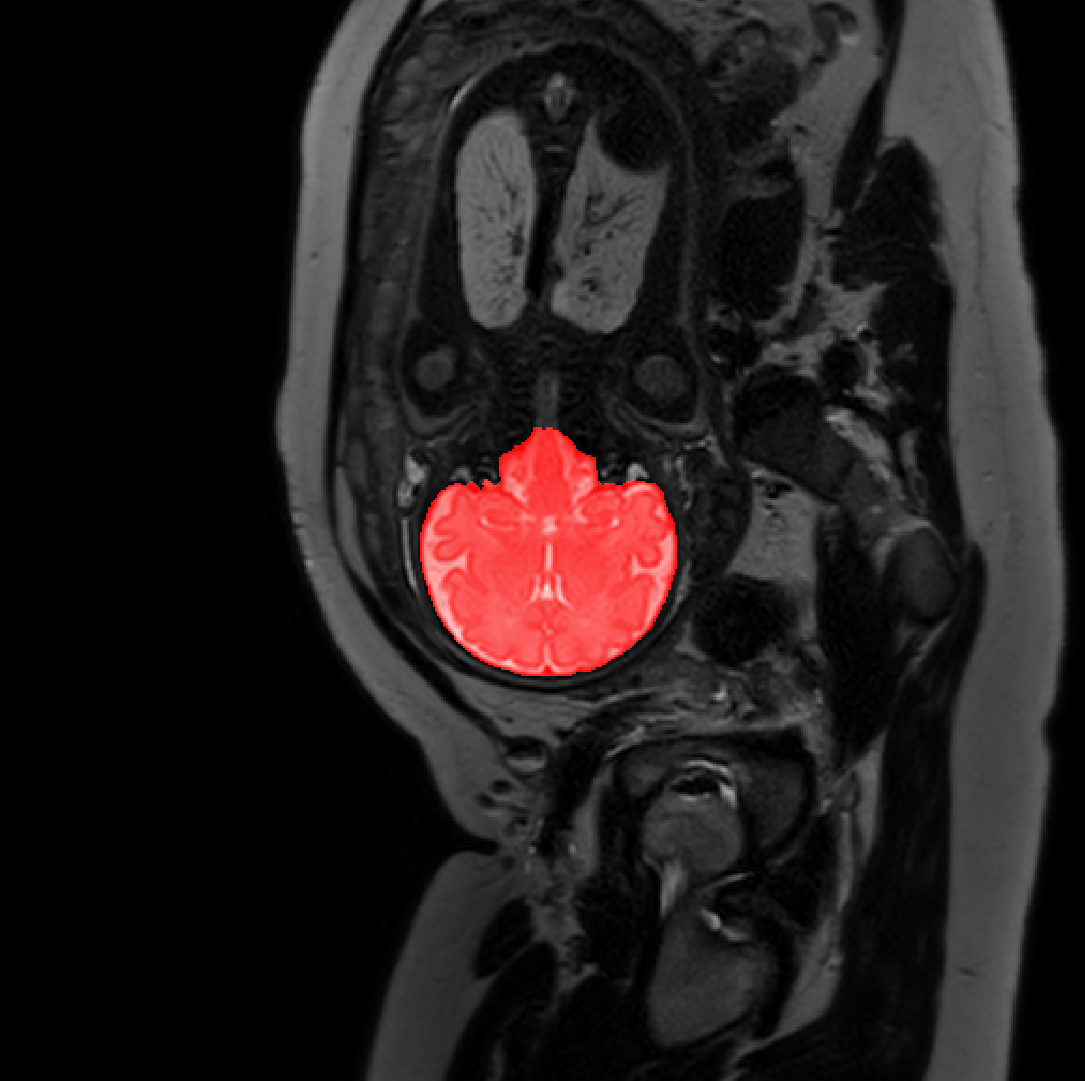

Table 1 lists average of quantitative evaluation results of these experiments and Figure 2 shows results obtained from each image. Figure 3 shows examples of the obtained segmentations.

Figure 3: Example of ICV segmentations in images acquired in axial (left), coronal (middle) and sagittal (right) planes. Top row: A slice from T2-weigted image; Second row: Automatic segmentations obtained using 7 training images from the representative imaging planes; Third row: Automatic segmentations obtained using all 21 training images from all 3 image orientations; Bottom row: Manual segmentation.